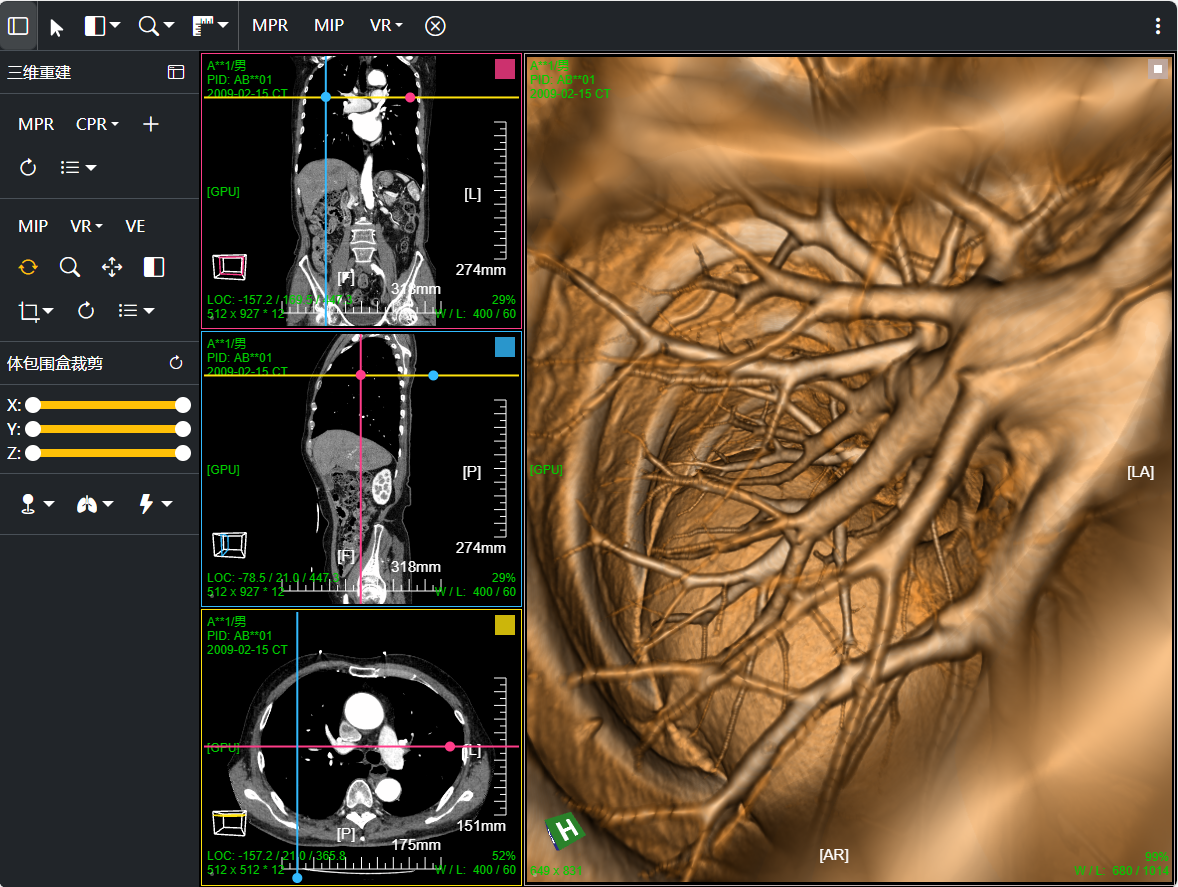

三维:MPR多平面重建(支持任意旋转)、CPR任意曲线切面重建、MIP最大密度、VR容积重建、VE虚拟内窥;任意三维裁剪、一键去床、一键去头骨、快速旋转、厚切MPR(最大密度/最小密度/均值/VR); 手工/半自动分割,分割目标三维渲染; 肋骨CPR拉伸渲染、牙神经管渲染、血管CPR拉直渲染等

八、三维浏览功能操作和截图

左键双击MPR窗口可在MPR三窗口和1x1窗口间切换;三维渲染窗口左键双击在在1x1视图模式和当前视图模式切换

VR容积渲染;鼠标右键默认实时调整当前VR传输函数

MIP 最大密度投影渲染: 鼠标右键默认实时调窗

VR渲染一键去床体:为提高去床速度,可先进行体包围盒裁剪选择含有床体的部分然后点击一键去床功能